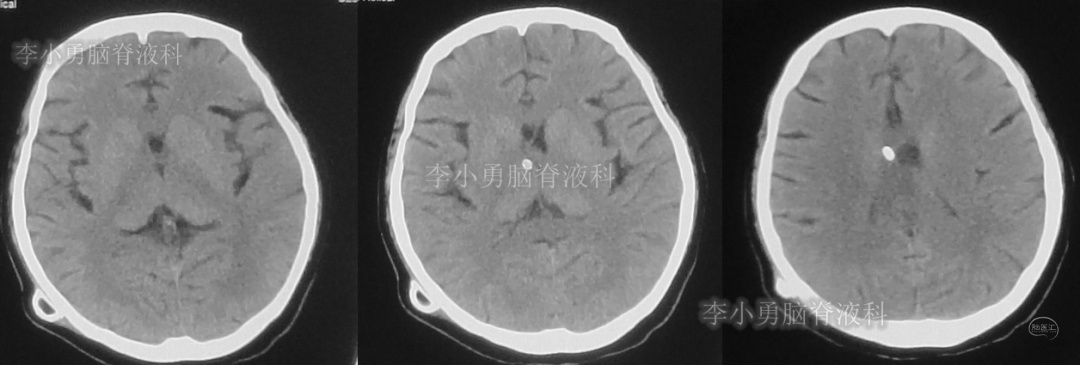

此后1个多月(2019年11月4日到2019年12月16日),患者意识一直无改善,一直呈模糊状态,多次复查头颅CT(图-12至图-20)见脑室大小反复变化不定,医生根据CT结果等反复多次调节分流泵压力(具体过程家属回忆不起)。但患者病情无好转却逐渐加重,逐渐不能咀嚼、吞咽及进食,卧床不起。

图-12:2019年11月8日头颅CT

图-13:2019年11月16日头颅CT

图-14:2019年11月19日头颅CT

图-15:2019年12月3日头颅CT

图-16:2019年12月10日头颅CT

图-17:2019年12月12日头颅CT

图-18:2019年12月13日头颅CT

图-19:2019年12月14日头颅CT

图-20:2019年12月16日头颅CT